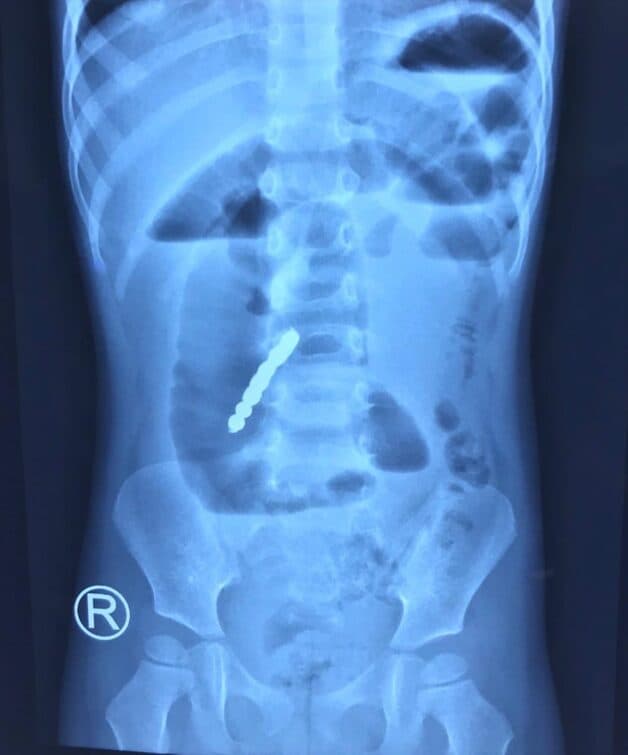

Bé 2 tuổi bị thủng ruột vì nuốt bi nam châm (Ảnh: Báo Lao Động)